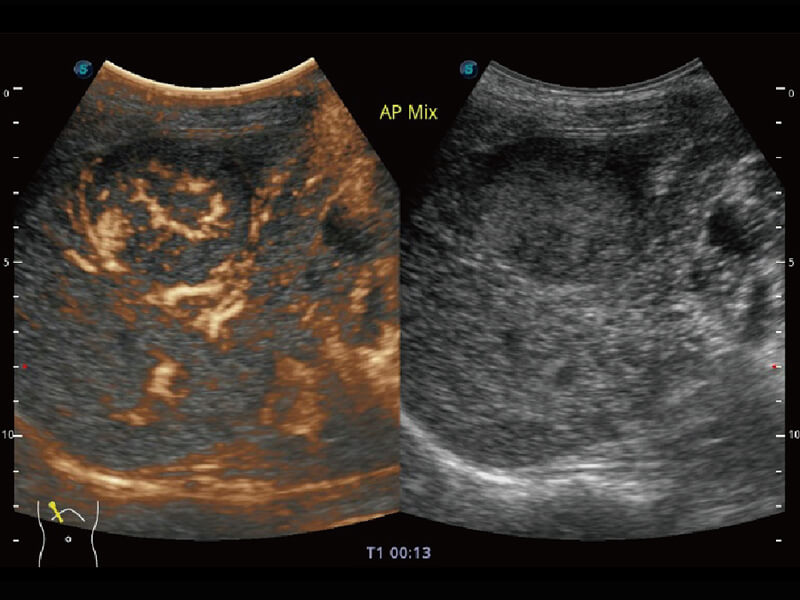

成像功能

性能优异的硬件架构,极大提升超声系统的运行效率和数据处理能力。相比以往超声成像系统,Wis+平台为您带来极快的响应速度和成像帧频,提升检查流畅度。